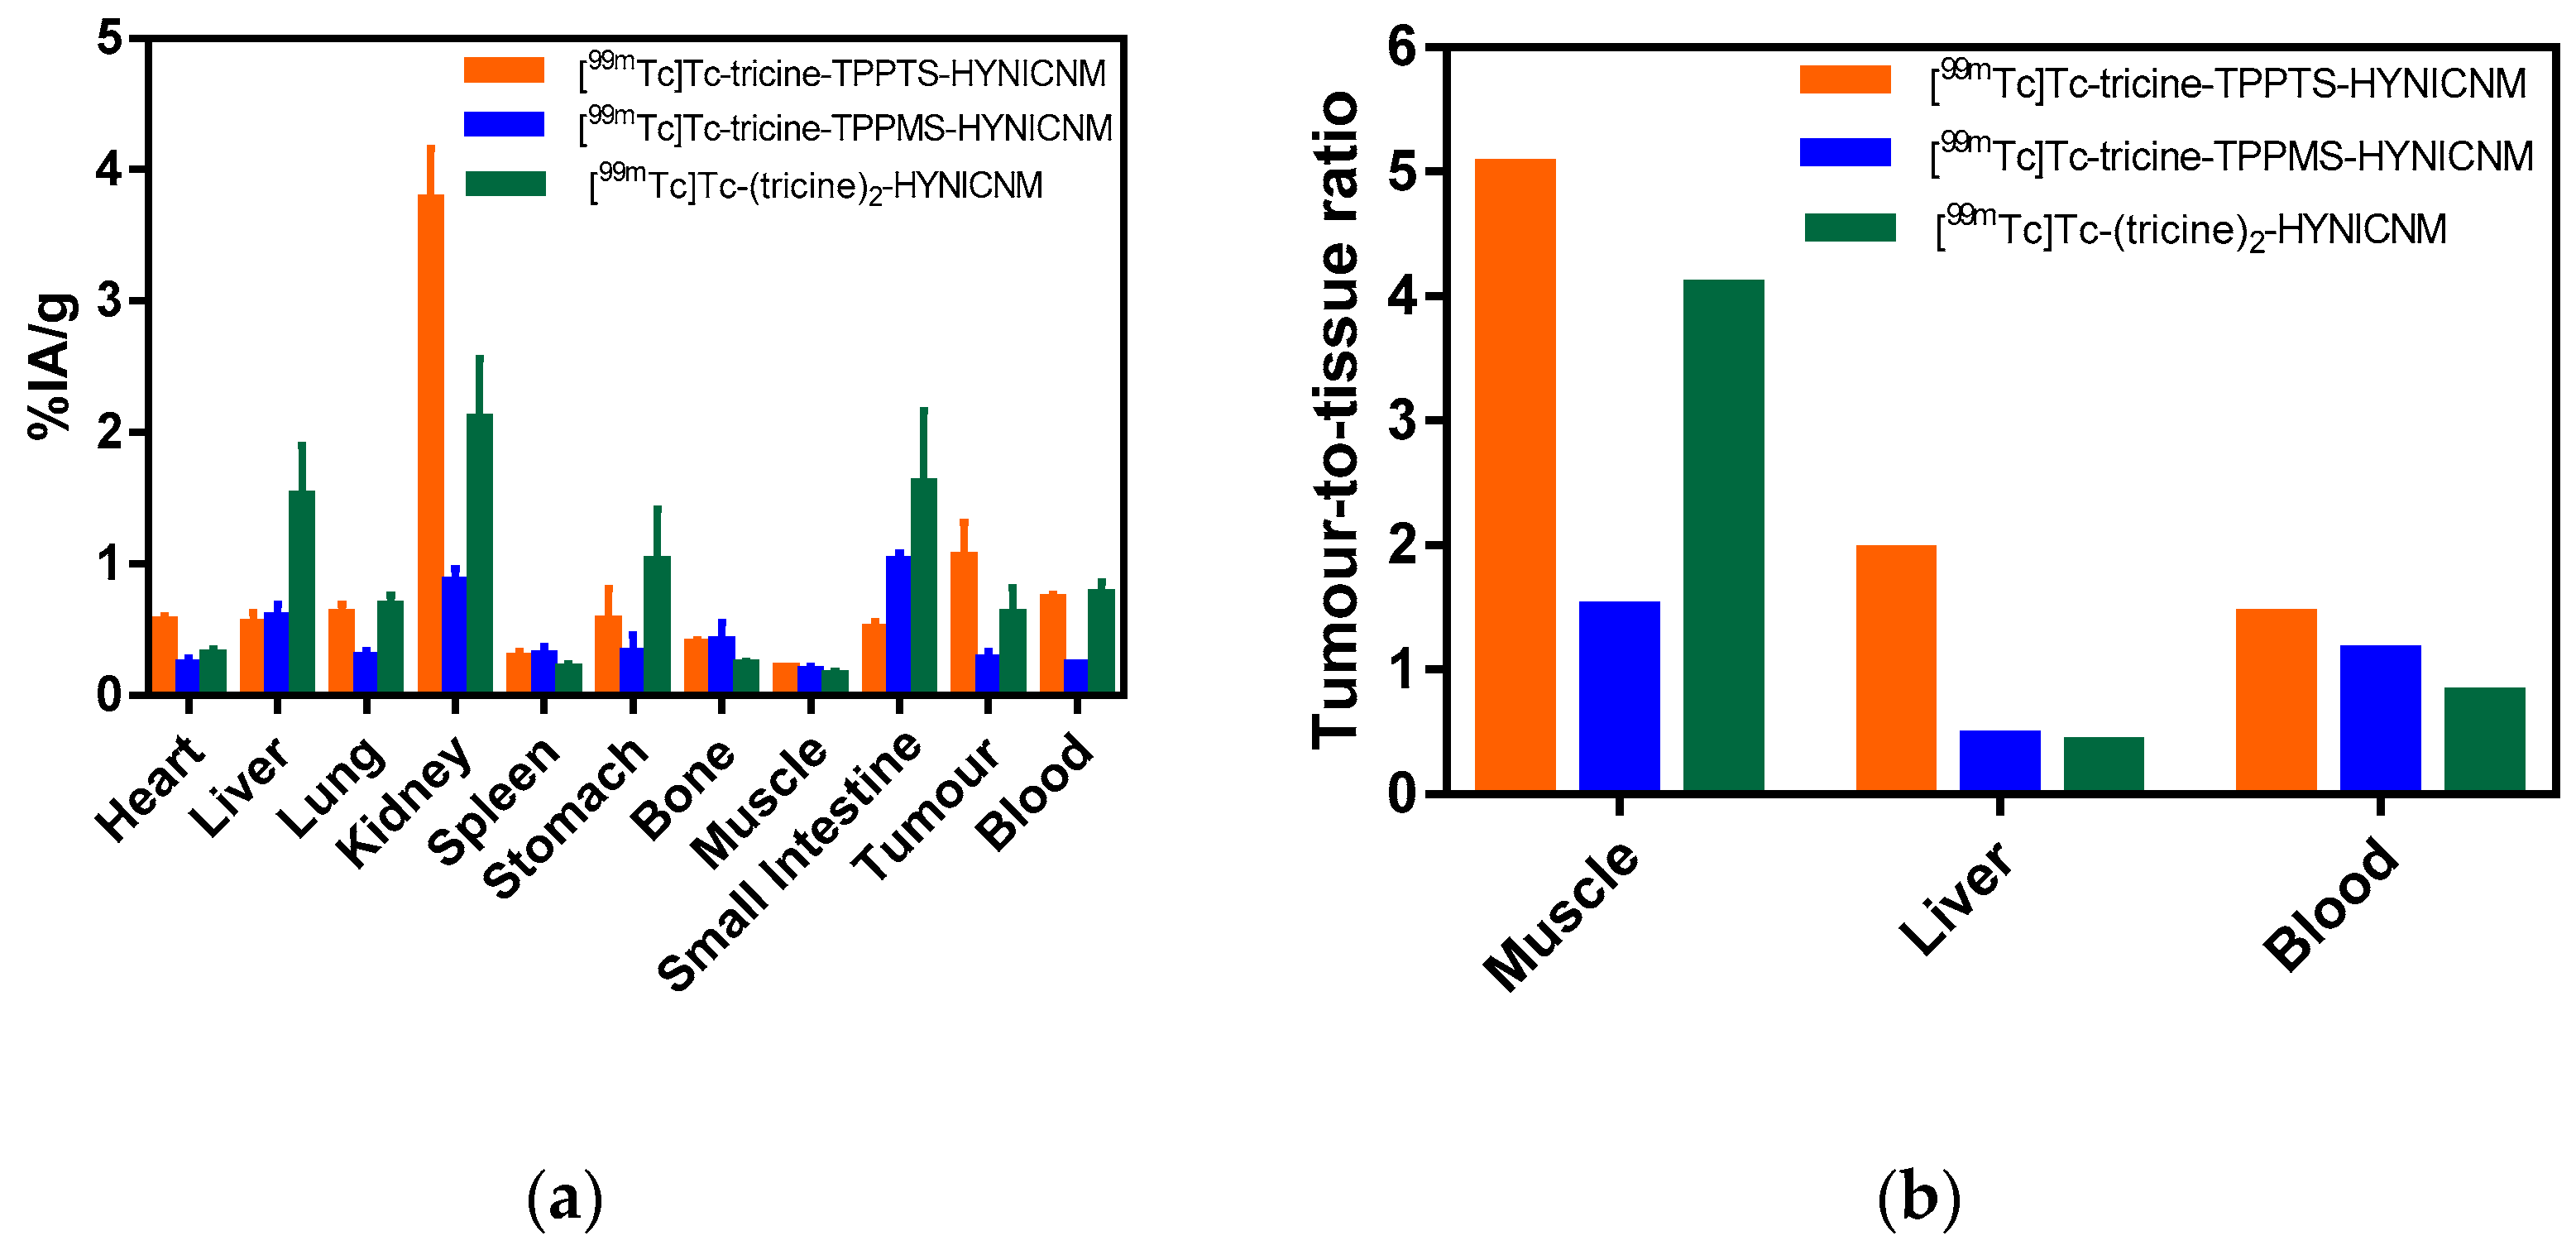

2.5. Biodistribution Studies

4.7. Biodistribution Studies